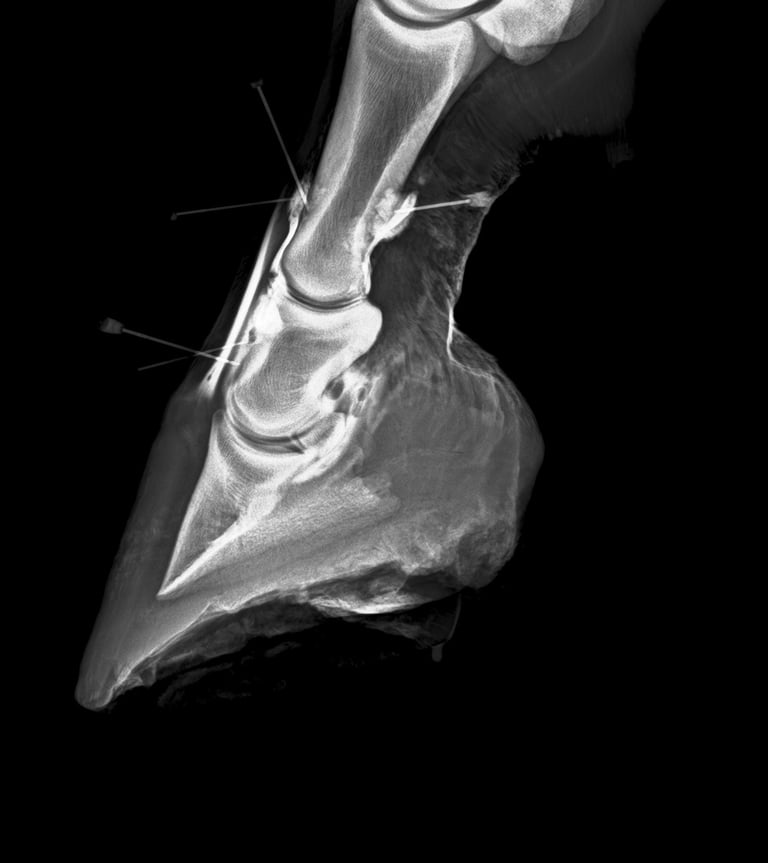

DIAGNOSTICO POR IMAGENES: ECOGRAFIA Y RADIOGRAFIA

Región femoro tibio rotuliana, anatomia, biomecanica y casos -

CURSO COMPLETO